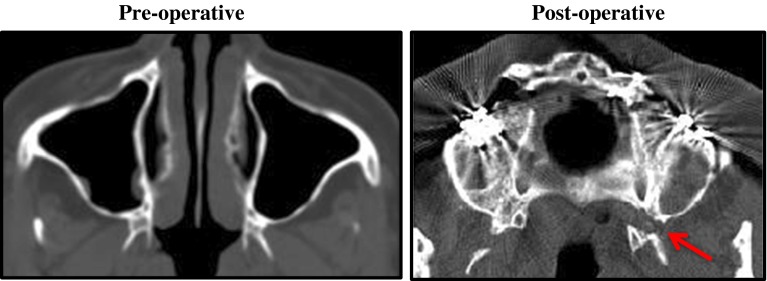

The other four patients (Group II) underwent Trimble technique in which a vertical cut is made on the tuberosity in the third molar region avoiding the pterygomaxillary junction. In this technique, after osteotomizing the lateral wall of the maxilla and lateral wall of the nose, and separating the cartilaginous septum and vomer, pterygomaxillary separation was achieved by making the cut in the tuberosity region distal to the second molar. Firm digital pressure in the area of the premaxilla was applied in an inferior direction in order to downfracture the maxilla. If the applied force did not result in downfracturing of the maxilla, the osteotomies were re-examined to ensure that they were complete. Pre-operative and post operative images of one patient are shown in Fig. 2.

Fig. 2.

Preoperative and postoperative CT images of a patient treated with Trimble technique. Arrow denotes the cut at the tuberosity

Although postoperatively, acceptable separation between the maxilla and the pterygoid plates was achieved and the maxillary segments could be moved to the postoperative ideal position in all 8 cases (16 sides), low level pterygoid plate fractures occurred (Table 1, Fig. 9) in 3 sides out of 8 in Group I. Fracture occurred in patients in whom thickness of the pterygomaxillary junction was less than or equal to 3.6 mm. In Group II, postoperative CT showed no pterygoid plate fractures. No other major complications such as skull base fractures were seen in postoperative CT scan in either of the two groups.

Fig. 9.

Postoperative CT showing left side lateral pterygoid plate fracture